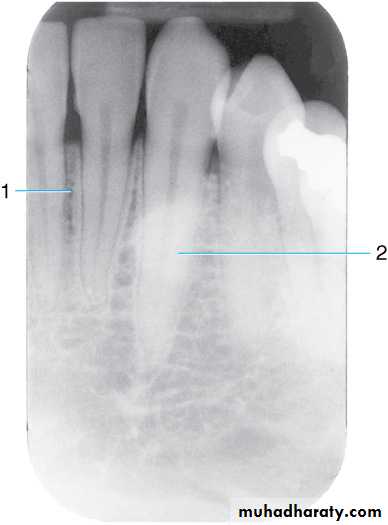

This radiograph shows (1) radiolucent restorations (composites) on the mesial surface of the lateral incisor and distal surface of the central incisor. Note that under both restorations is a base of radiopaque material. (2) The radiolucencies on the mesial surfaces of both central incisors are carious lesions.

Retention pins. (1) Radiopaque pins help retain the radiolucent composite restorations. (2) Small radiopaque amalgam restorations.